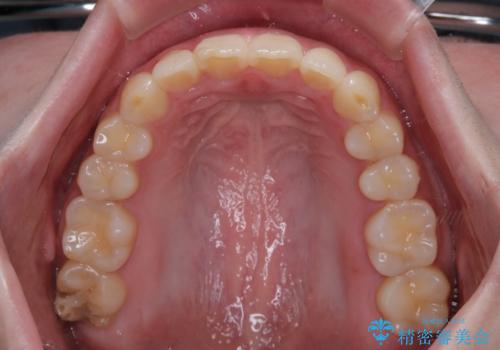

前歯のデコボコをインビザラインできれいに整える

前歯の捻れを改善するとともに、口元が少しでも引っ込むように治療計画を立て、仕上げることができました。

長時間の装着や、定期的な来院がままならず、想定よりも長期間の治療となってしまいました。